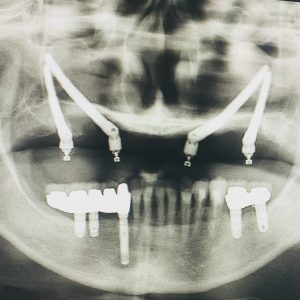

- ●得意とされるのは咬合再構成・骨造成・オールオン・ザイゴマ等の難症例

オールオンも上顎両サイドに2本足して、上6下4の10本埋入を得意とされています。オールオンの症例が年間100症例ほど、ザイゴマインプラントは年間100本ほどで、全国でもトップクラスの先生です。

吉留先生のサンプル症例

こちら↓に先生の症例をサンプルとして、説明と一緒に掲載してあります。ご一読ください。